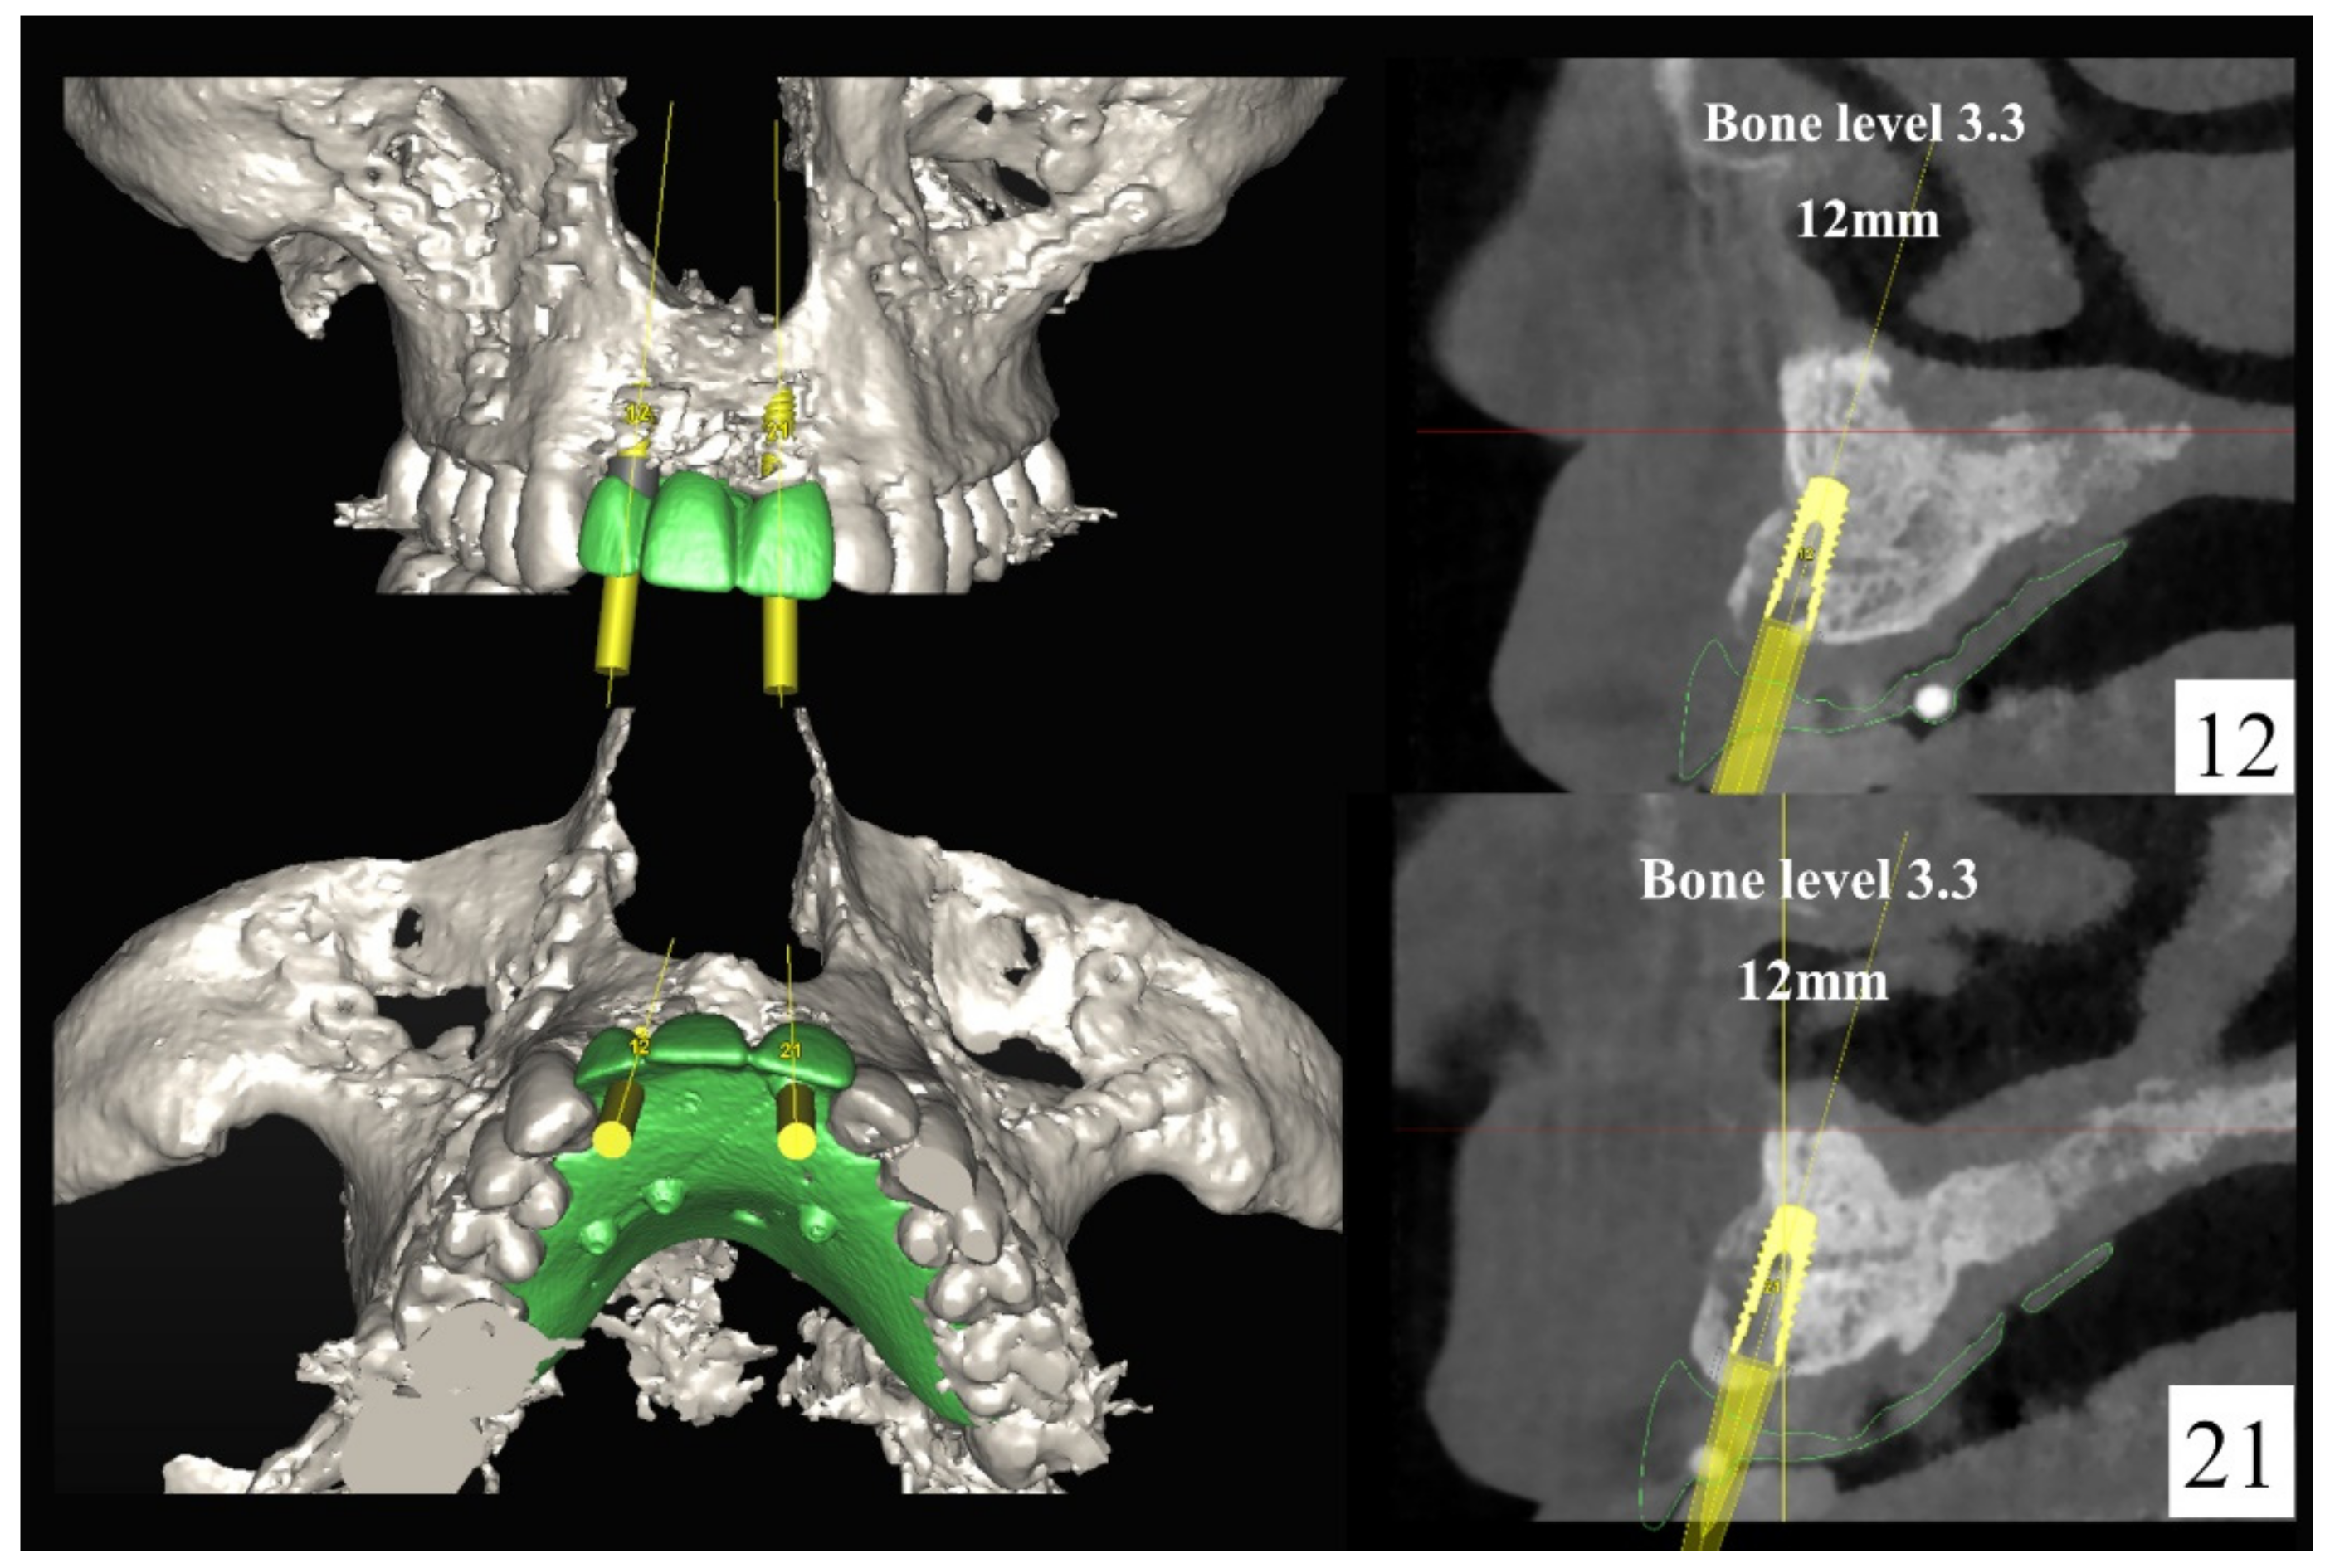

6.2.3. Image Segmentation and Virtual Planning:

6.2.4. Intra-Operative Documentation: